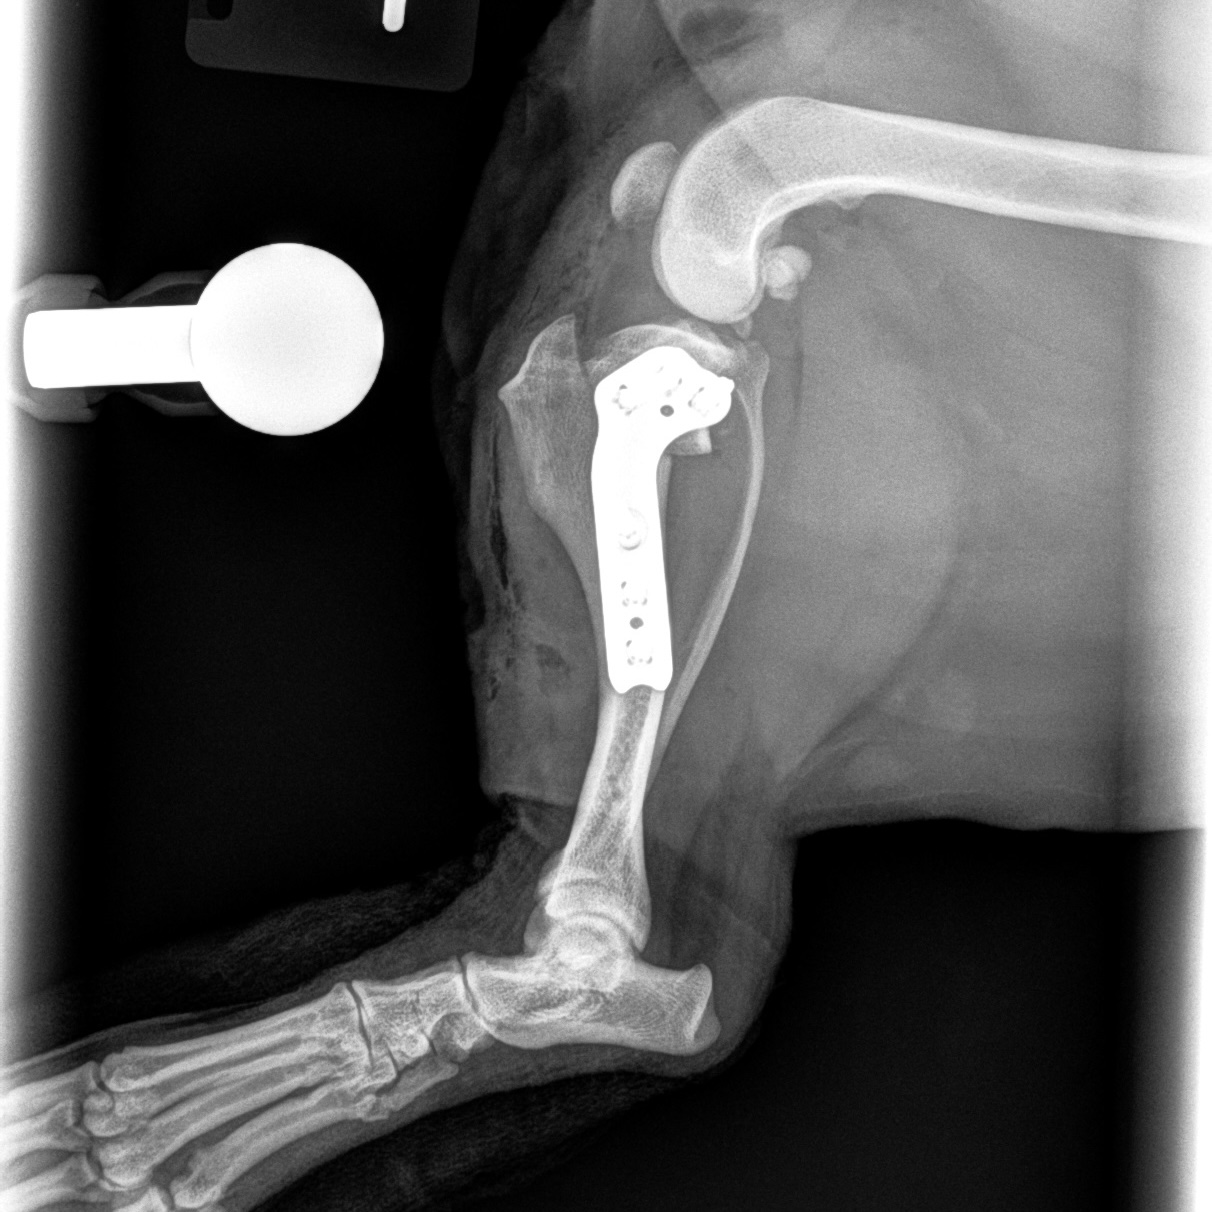

Femoral Head Ostectomy (FHO) Surgery

FHO surgery is an option for pets with severe hip pain due to conditions such as hip dysplasia, trauma, or chronic arthritis. By removing the damaged portion of the hip joint, pain can be significantly reduced, allowing many pets to regain comfortable mobility with proper rehabilitation.

Femoral Head Ostectomy (FHO) Before Surgery

Femoral Head Ostectomy (FHO) After Surgery

Femoral Head Surgically Removed